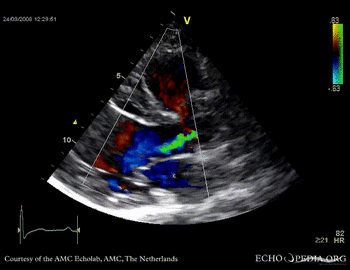

PLAX showing concentric left ventricular hypertrophy PLAX shows aortic regurgitation